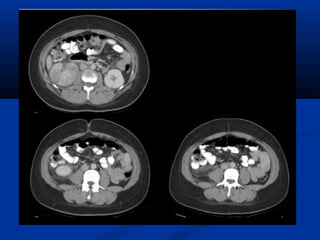

Aùp xe thaän vaø quanhAùp xe thaän vaø quanh

thaänthaän

- Do ñieàu trò vieâm ñaøi thaän khoâng ñuùngDo ñieàu trò vieâm ñaøi thaän khoâng ñuùng

caùch hoaëc khoâng ñuùng möùc, ñöa ñeáncaùch hoaëc khoâng ñuùng möùc, ñöa ñeán

hoaïi töû nhu moâ thaän keøm taïo aùp xe.hoaïi töû nhu moâ thaän keøm taïo aùp xe.

- Yeáu toá nguy cô: tieåu ñöôøng, taéc ñöôøngYeáu toá nguy cô: tieåu ñöôøng, taéc ñöôøng

tieát nieäu, soûi thaän nhieãm truøng, suy giaûmtieát nieäu, soûi thaän nhieãm truøng, suy giaûm

mieãn dòch, suy nhöôïc cô theå…mieãn dòch, suy nhöôïc cô theå…

- Aùp xe quanh thaän do thaän öù muû bò vôõ,Aùp xe quanh thaän do thaän öù muû bò vôõ,

hoaëc do lan tröïc tieáp töø nhieãm truønghoaëc do lan tröïc tieáp töø nhieãm truøng

phuùc maïc hoaëc sau can thieäp phaãu thuaät,phuùc maïc hoaëc sau can thieäp phaãu thuaät,

noäi soi, thuû thuaät qua da…noäi soi, thuû thuaät qua da…

 Sieâu aâm:Sieâu aâm:

- Khoái phöùc taïp, daïng troøn, thaønh daøy,Khoái phöùc taïp, daïng troøn, thaønh daøy,

thöôøng taêng aâm phía sau.thöôøng taêng aâm phía sau.

- Coù theå thaáy chaát caën laéng chuyeånCoù theå thaáy chaát caën laéng chuyeån

ñoäng beân trongñoäng beân trong

- Ñoâi khi hieän dieän khí beân trong vôùi boùngÑoâi khi hieän dieän khí beân trong vôùi boùng

löng dôlöng dô

- CÑPB: nang thaän nhieãm truøng hoaëc xuaátCÑPB: nang thaän nhieãm truøng hoaëc xuaát

huyeát, nang kyù sinh truøng, nang ña thuøy, uhuyeát, nang kyù sinh truøng, nang ña thuøy, u

taân sinh daïng nang.taân sinh daïng nang.

- Sieâu aâm coù vai troø theo doõi bn ñang ñöôïcSieâu aâm coù vai troø theo doõi bn ñang ñöôïc